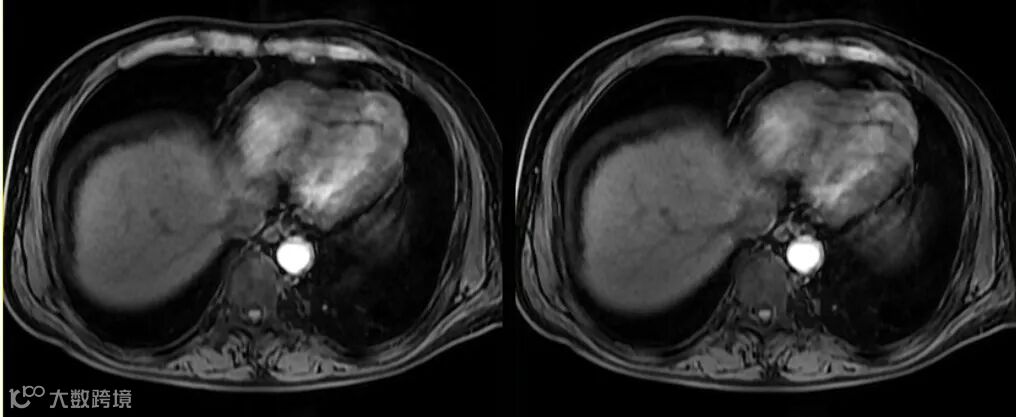

在增强机理方面,MRI“对比剂”与CT“造影剂”有着本质的区别。钆对比剂本身并不会产生信号,而是当钆对比剂与水分子的距离足够近时,通过缩短周围水质子的T1弛豫时间来间接产生“增强”的作用。切记不要以信号强度的高低来判定摄取对比剂浓度的多少。